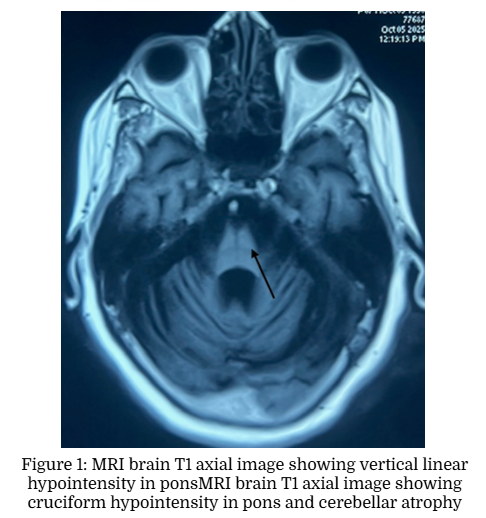

Hot Cross Bun Sign

Somarajan Anandan Sajeesh Rajendran Anandhu Suresh Joesni Joy

A Case Report | 30 Jan 2026